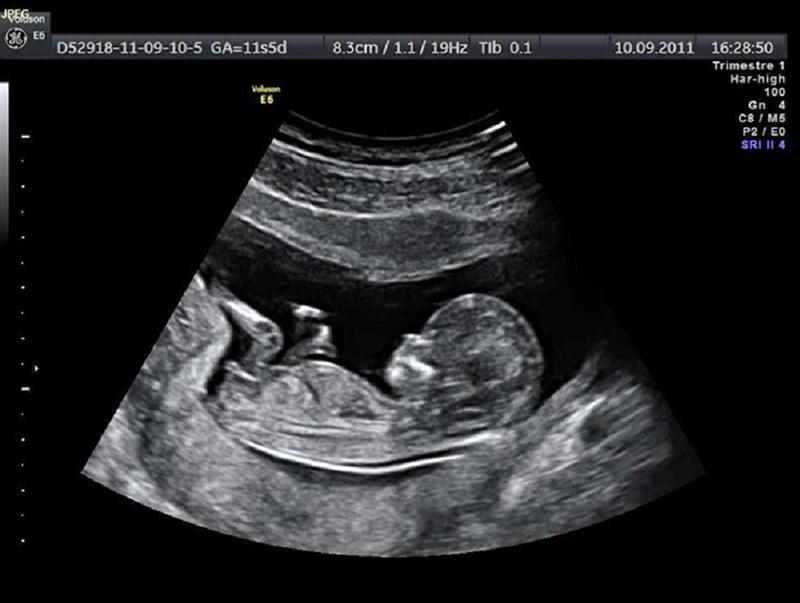

The cycling community erupted in emotion after golden couple Julian Alaphilippe and Marion Rousse revealed they are expecting their third child. The announcement came with an adorable ultrasound photo that went viral instantly, amassing over 500,000 likes within two hours.

Now, as Marion enters her second trimester, Julian has reportedly scaled back his training schedule to spend more time with his family. “For once,” he said, laughing, “I’m happy to lose to love.”